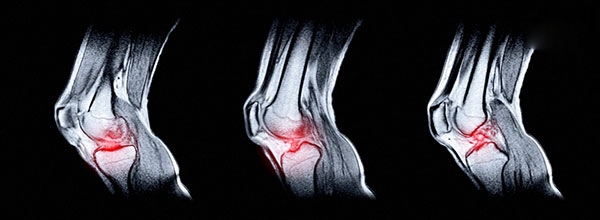

Xét nghiệm hình ảnh: Chụp X-quang, chụp cắt lớp vi tính (CT) hoặc chụp cộng hưởng từ (MRI). Các xét nghiệm này có mục đích kiểm tra gai xương, tổn thương xương dưới sụn, đánh giá mức độ tổn thương mô mềm, tình trạng hao mòn sụn và những bất thường khác khiến quá trình tiết dịch khớp không diễn ra.